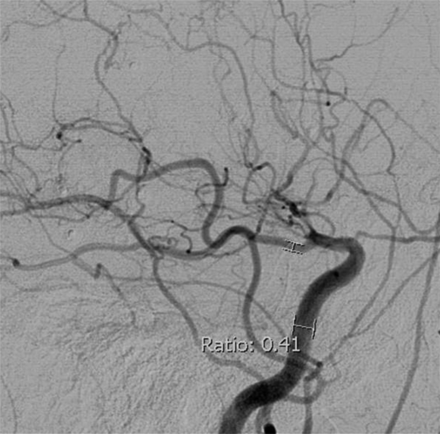

2) Ratio of the PcomA lumen diameter to the ipsilateral precavernous ICA lumen diameter21 is shown in Fig 2. Because the distal ICA is stenosed in MMD, the ICA measurement was performed at the precavernous portion with the widest, parallel lumen. If a PcomA infundibulum was present, the diameter was measured distal to infundibulum.

PcomA/ICA ratio method. Lateral projection from DSA with the PcomA/ICA ratio in a patient with MMD with distal ICA occlusion beyond the PcomA origin.